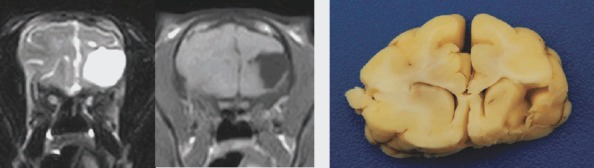

The age of the cat is important information in drawing up the differential list. As some diseases more commonly affect younger cats and others, older cats. The diseases of the young animals are mainly the anomalous, congenital or infectious diseases. Multiple littermates can be affected and the only complaint is the seizure activity in many cases. The adult and old cats suffer more common inflammatory or neoplastic disease. The classical examples are anomalous/congenital diseases, usually diagnosed in kittens, that should not be firstly considered as a differential diagnosis for older cats with seizures. A number of different congenital brain malformations can cause seizures in young kittens; these include hydrocephalus, porencephaly, lissencephaly and others. Cats with porencephaly have cystic cavities within their cerebrum, and intrauterine feline parvovirus infection of the queen has been postulated as a possible cause for this (Summers et al, 1995) ( Figure 1 ). Treatment is aimed at controlling the seizures, and the prognosis will depend on the response to treatment. Cats with an obstructive hydrocephalus may require surgical placement of a shunt to drain the excess cerebrospinal fluid from the ventricular system to the peritoneum (ventriculoperitoneal shunt). Although this is preferential treatment in cats with congenital hydrocephalus, it is not treating the primary condition and is only palliative. However, the outcome is good if no complications of the shunt device do occur. Some patients can be managed conservatively, mainly with the drugs decreasing the production of cerebrospinal fluid (CSF).

Figure 1.

(From left to right) T2 weighted and T1 weighted transverse MRI images of a cat with porencephaly (PCR cerebrospinal fluid was positive for feline parvovirus). Gross post‐mortem ventral view of the brain of a cat with porencephaly